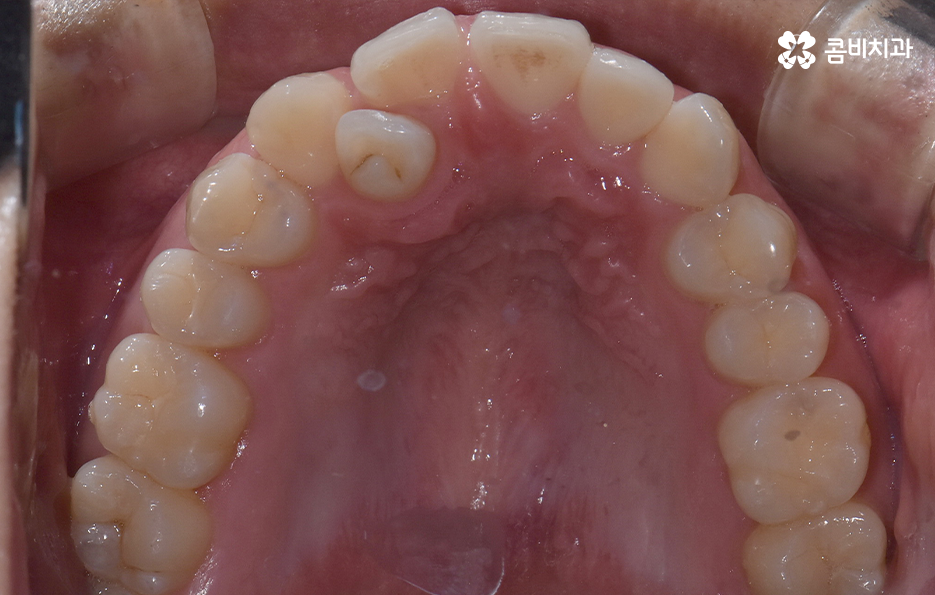

덧니가 나는 원인은 유전적인 영향부터 골격적인 부분 등 다양하지만 기본적으로는 치아가 나올 공간이 부족해서 덧니의 형태로 영구치가 자라는 경우가 많기 때문에 덧니 교정 사례에는 유독 발치 교정 사례가 많이 있는데요

요즘은 앞니만 약간 벌어져도 교정을 하는 분들이 크게 늘고 있기 때문에 덧니가 심하지 않아도 교정을 하는 분들도 많기 때문에 덧니 교정 사례에서도 비발치 사례도 많지만 보편적으로 덧니 발치교정 사례가 많은 것도 사실이기 때문에 어떠한 경우에는 발치교정이 필요하며 또한 어떻게 치아교정 계획을 세우는 것이 좋을지 오늘 포스팅에서 알아볼 거예요

다만 덧니 교정 사례에서 발치교정 사례가 많은 이유는 턱뼈가 좁아서 치아가 덧니로 자란 경우가 많기 때문에 치열을 재배열하기 위해서는 치아가 움직일 수 있는 충분한 이동공간이 필요하기 때문에 공간 확보의 목적으로서 작은 어금니 양옆, 위아래 4개를 발치를 하는 발치교정법이 보편적으로 많이 활용되고 있으며 치아의 이동 공간을 확보하는 방법으로는 발치 교정법 외에도 악궁확장, 어금니 후방이동, 치간삭제와 같은 비발치적인 방법도 가능하기 때문에 치아를 얼마나 이동시켜야 할지에 따라서 치료법은 개인차가 발생되고 있어요